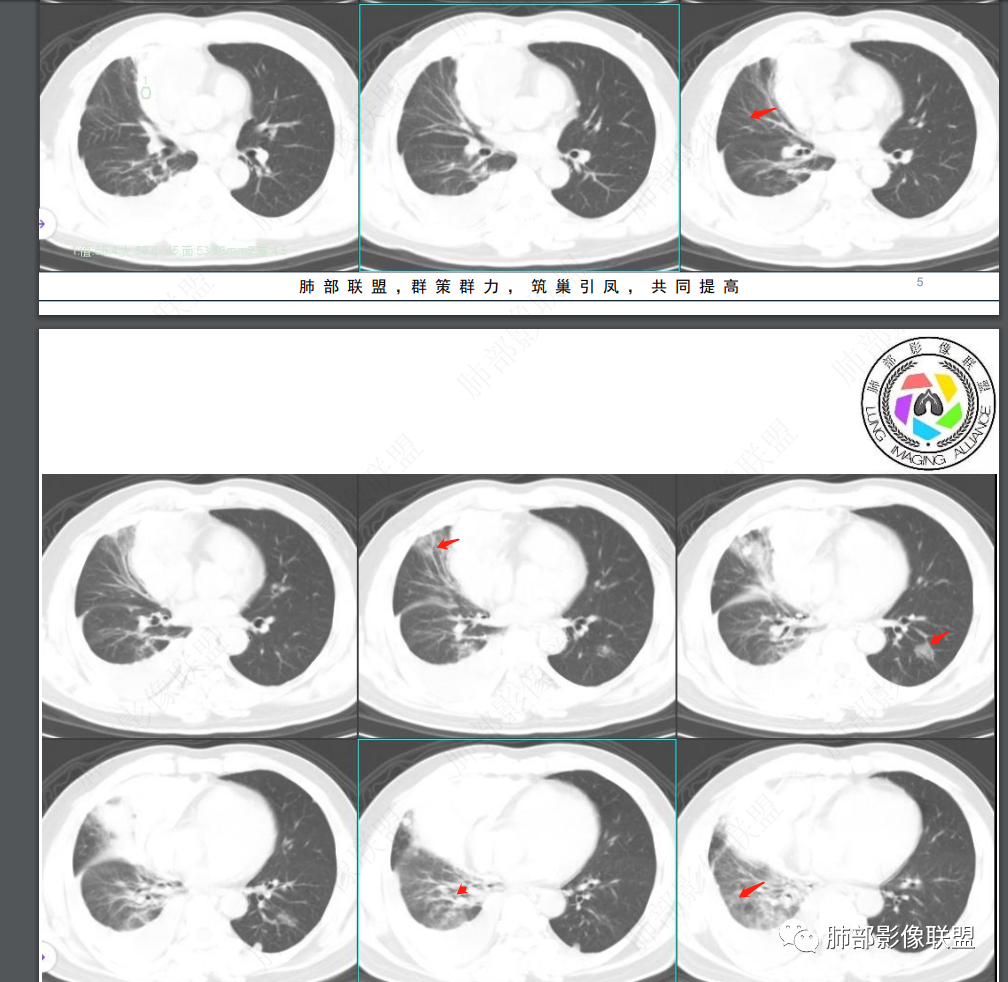

肺内是不是出血?胸膜多发结节,考虑转移瘤。定位前纵隔。考虑恶性肿瘤破裂出血并胸膜转移

2、CT图像所见:前中纵隔肿块,偏于右侧生长,平扫及增强扫描见肿块形态欠规则,密度欠均匀,内部见低密度坏死区,实性部分及分隔可见轻中度渐进性强化,内部可见细丝状、短条状明显强化小血管影,肿块外侧见弧形高密度无强化影(其与纵隔肿块间脂肪间隙清晰),考虑为出血;右肺中上叶含气不良。右侧胸腔见高密度积液,从平扫到增强扫描短时间量明显增加,符合急性出血。肺窗见双肺胸膜下多发结节,右肺大片状磨玻璃影,左肺下叶磨玻璃结节。

3、综合分析:本例右前上纵隔肿块,内部坏死,实性部分中度渐进性强化,内部可见细丝状明显强化小血管影。肿块与周围血管分界尚清楚,周围脂肪间隙显示不清,邻近胸膜显示增厚,结合瘤体内出血,破入或渗入右侧胸腔,双肺胸膜下结节影,符合恶性肿瘤转移。

胸腺类癌好发于40~60岁男性,男女比例约为3:1。胸腺类癌侵袭性较胸腺癌低,属于低至中等程度恶性肿瘤。但是约80%侵犯邻近组织结构,20%~40%发生胸内淋巴结或远处转移,转移部位主要包括肺脏、骨、肝脏、脑等,一般表现为椎体成骨性转移。